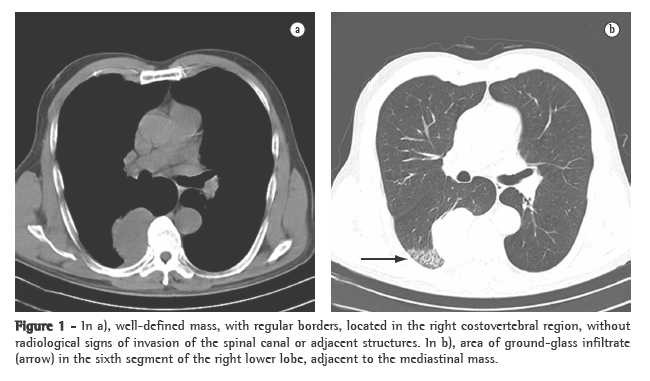

A physical examination revealed good general health and nutritional status, and vital signs were normal. The patient presented no lymph node enlargement. Upon pulmonary auscultation, there were fine inspiratory rales throughout both lung bases. The cardiac auscultation was normal. Examination of the abdomen and lower limbs revealed no alterations. The results of the blood workup and biochemical analyses were within the limits of normality. A CT scan of the chest (Figure 1a) revealed a well-defined mass, with regular borders, in the right costovertebral region, measuring 6 × 4.3 cm. Adjacent to the mass, we observed pulmonary infiltrates, apparently inflammatory and nonspecific (Figure 1b).